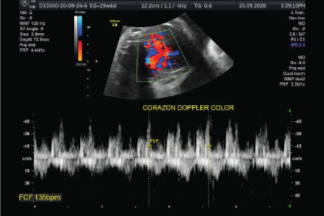

Permite evaluar y medir el flujo sanguíneo de las válvulas y las cavidades del corazón del bebé, de esta manera, se puede determinar si su corazón está funcionando correctamente.